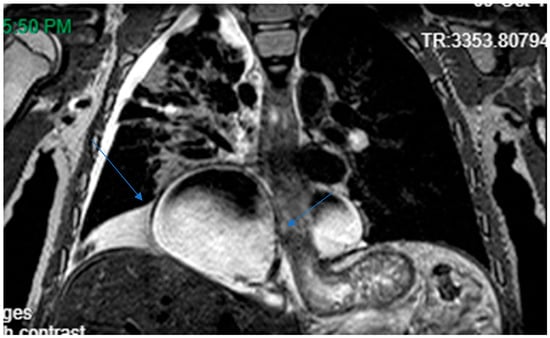

Hennekam lymphangiectasia–lymphoedema syndrome (HLLS) is a genetically heterogeneous autosomal recessive disorder characterised by generalised lymphatic dysplasia of the intestine, limbs, pericardium and pleural space (see Scheme 1 and Scheme 2). Affected children suffer congenital lymphoedema, facial dysmorphism and variable intellectual disability []. Facial anomalies included a flat face, flat nasal bridge, hypertelorism, epicanthal folds, small mouth, tooth anomalies, and ear defects (Scheme 2). Hypothyroidism is not infrequent.

Scheme 1.

Capsule endoscopy image showing extensive intestinal lymphangiectasia (with permission).

Scheme 2.

MRI chest showing right basal cystic lesion extending into medial left lung (with permission).